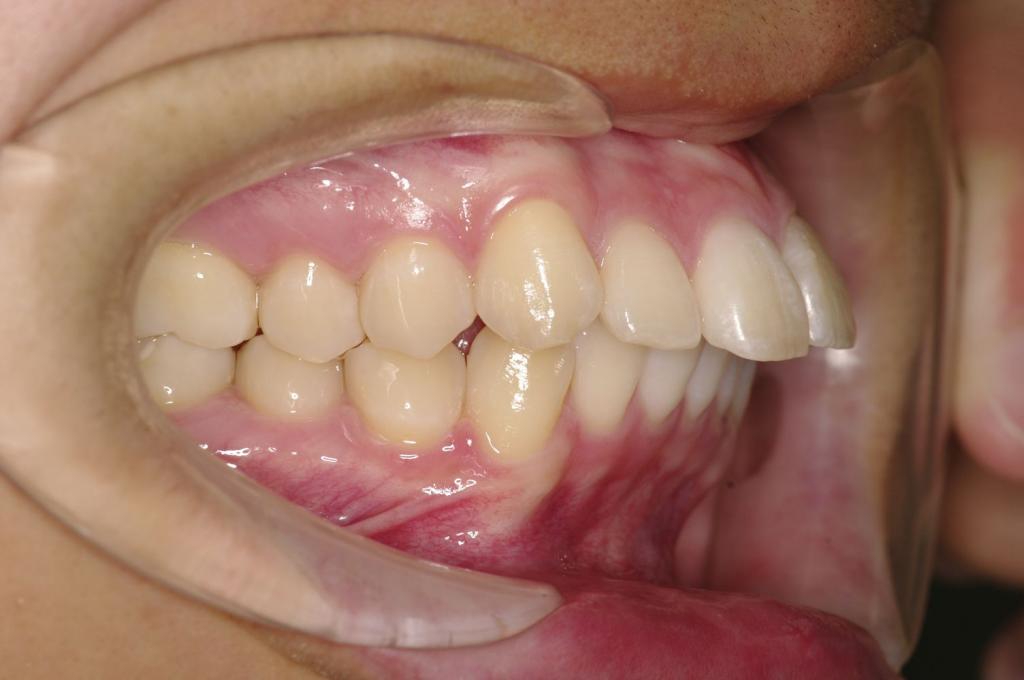

前歯、出っ歯・開咬の矯正治療

(治療期間、治療前後写真、治療方法、費用)WORKS